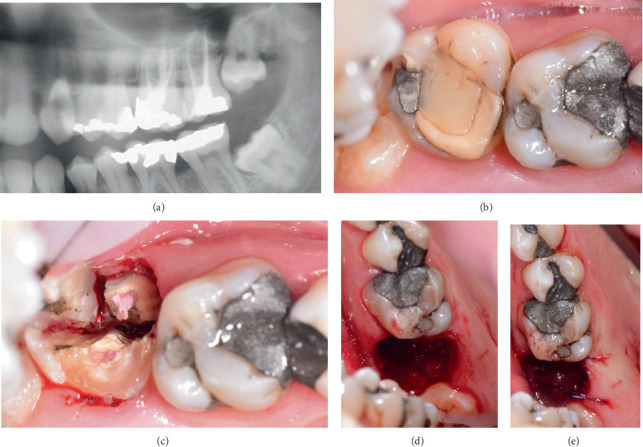

Tooth autotransplantation is a procedure in which a donor tooth is transplanted within the same patient's jaw to replace a missing tooth. Donor tooth root morphology and periodontal ligament integrity are key factors influencing success. We report a semi-immediate autotransplantation of a maxillary third molar with a 90° divergent root into a site previously affected by a periapical abscess. After the extraction of the compromised tooth (#15) and removal of the interradicular septum, the site was left to heal to allow soft tissue closure and infection resolution. During this period, CBCT imaging and a 3D-printed donor tooth replica (CARP model) were used to plan the procedure, including the intended root amputation. Two weeks later, autotransplantation was performed. The recipient site only required soft tissue and granulation tissue management, with no additional bone preparation, allowing for a minimally traumatic approach. The donor tooth was transplanted with an extraoral time of under 6 min. At the 18-month follow-up, the tooth remained functional, asymptomatic, and radiographically stable. This case highlights the feasibility of delayed autotransplantation following infection and the clinical value of combining imaging with prototyping in surgical planning-particularly when dealing with donor teeth with unfavorable root anatomy.